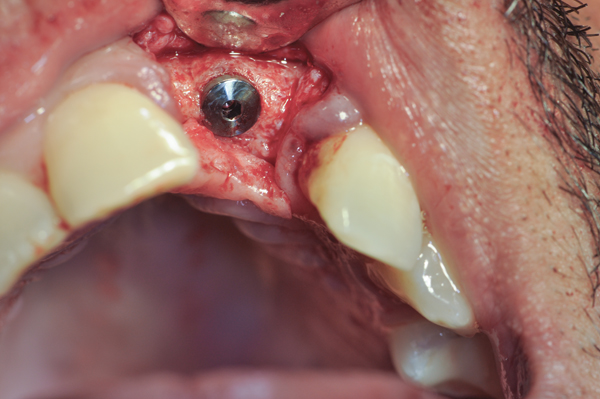

Fig 11. An implant was placed in regenerated bone.

Figure 11